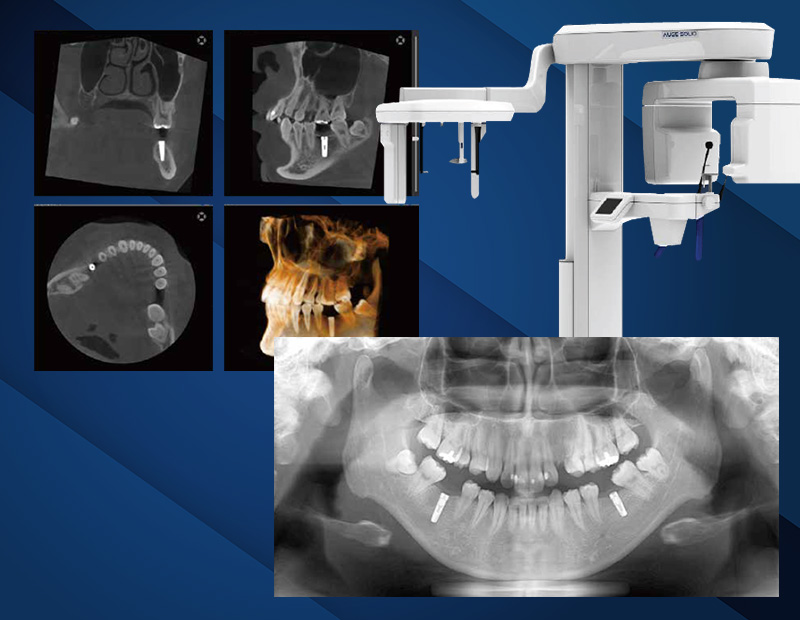

より安全に精度の高いインプラント手術を行うためには、CT撮影による画像診断が必要不可欠です。CT撮影を行うことで三次元的に骨の状態を診断することもでき、患者様の口腔状態に応じた治療計画の提案が実現できます。

また、インプラント手術を行う上で、上下顎の構造や神経の位置、骨密度、インプラントの適切な埋入位置など、把握・確認すべき点が多々ありますが、CT撮影を行うにより、これら内容を正確に把握し、術前に検査・診断の上、患者様みなさまにより安全な治療提供が可能となります。